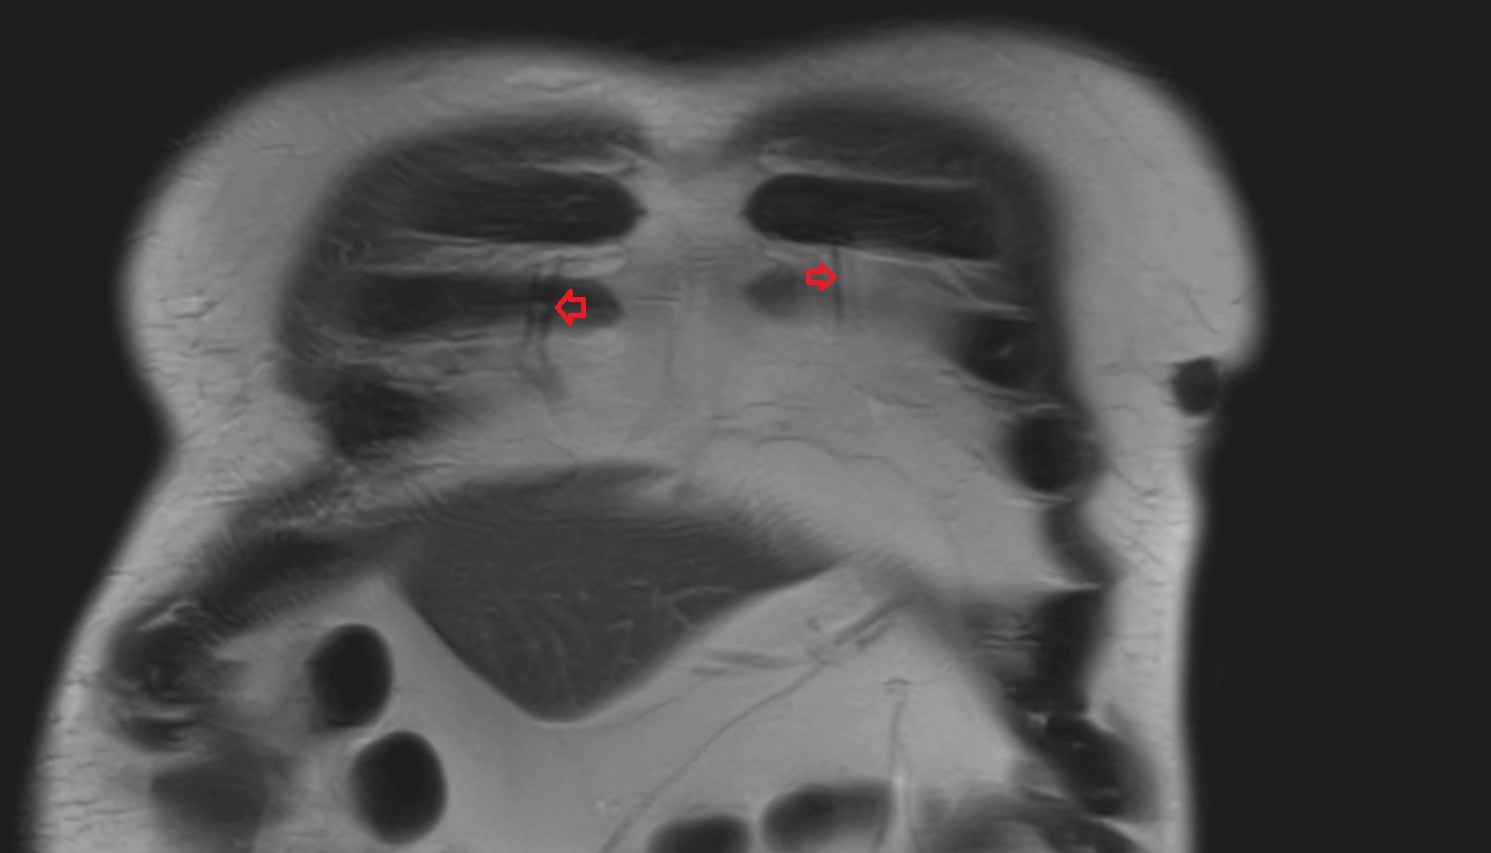

- Manubrium of sternum

- Sternocostal synchondrosis of first rib